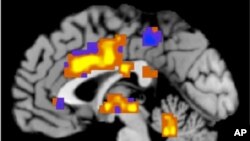

แพทย์สามารถพิสูจน์ได้ว่าการที่ผู้ป่วยบันทึกอาการขี้ลืมตั้งแต่ระยะเริ่มแรกสามารถบอกสัญญาณโรค Alzheimer ได้แต่เนิ่นๆ ซึ่งการทดลองพบว่าการตรวจสอบความจำของตนเองที่เริ่มเสื่อมเป็นหลักฐานที่ชี้ถึงโรค Alzheimer ได้ 6 ปีให้หลัง

แพทย์หญิง Rebecca Amariglio จาก Brigham and Women’s Hospital ที่นคร Boston กล่าวว่ากลุ่มเสี่ยงของโรคนี้มีโปรตีนที่เรียกว่า beta amyloid ในสมองซึ่งนักวิทยาศาสตร์เชื่อว่าเกี่ยวโยงกับโรค Alzheimer

ปัจจุบันนี้การวิจัยทางการแพทย์มุ่งความพยายามไปที่การหาคำตอบว่าความจำเสื่อมที่นำไปสู่โรค Alzheimer เริ่มต้นขึ้นเมื่อใด เพราะหลายครั้งกว่าจะตรวจพบผู้ป่วยได้สูญเสียความสามารถด้านความทรงจำไปมากแล้ว

ดังนั้นวิธีบันทึกอาการหลงลืมของตนเองโดยผู้ป่วยซึ่งสามารถบ่งบอกถึงอาการที่เรียกว่า subjective cognitive decline จึงเป็นประโยชน์ต่อแพทย์ในการวินิจฉัยต่อไปว่าผู้ป่วยเป็นโรค Alzheimer หรือไม่